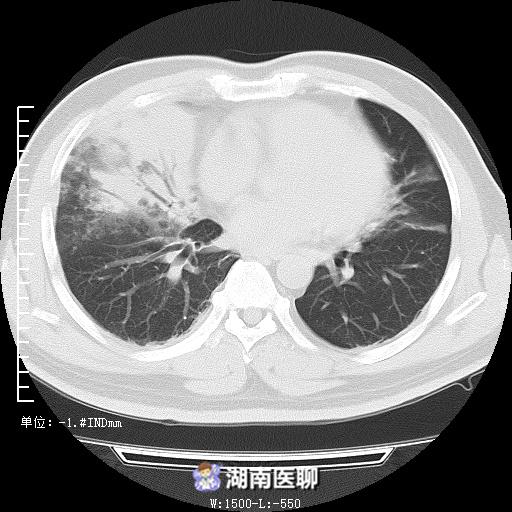

被紧急送往湖南省职业病防治院,检查显示血气提示氧分压59mmHg(正常值80 mmHg),肺部CT:双肺渗出病变及实变。

(起病时肺部CT)